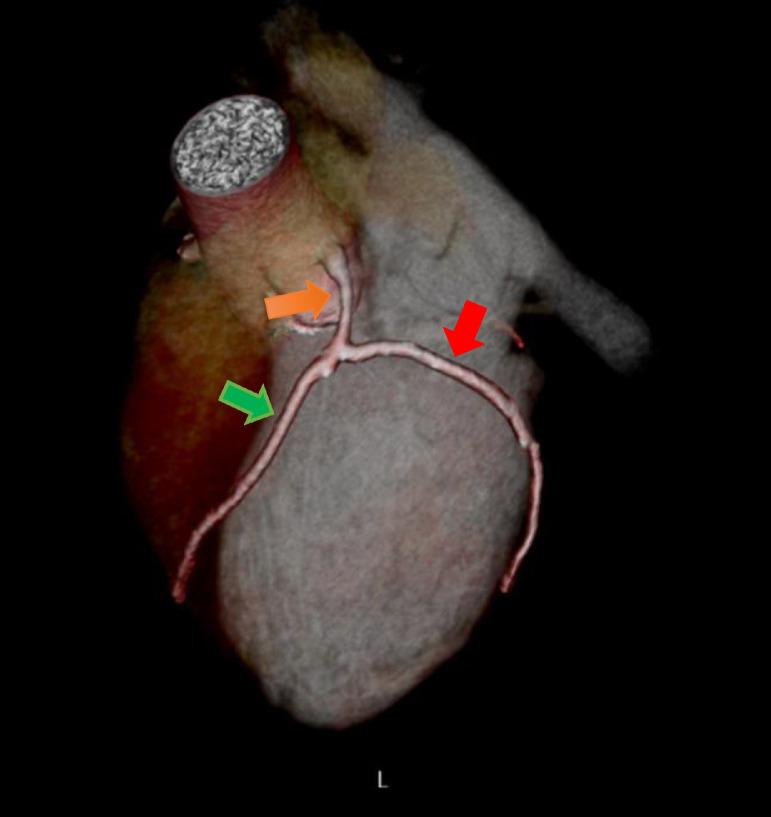

Blunt chest trauma may cause variable degrees of thoracic injuries. Most of the patients may remain asymptomatic after sustaining blunt chest trauma. But in rare instances, life-threatening conditions such as coronary artery dissection may occur. The authors present a 29-year-old male adult with persistent chest pain following blunt trauma with a rise in cardiac troponins and elevated ST segment in ECG. Coronary CT and conventional angiography demonstrated dissection of the left main coronary artery. It is deemed necessary to suspect cardiac injury in patients with a history of blunt chest trauma in appropriate clinical settings. Early recognition of coronary artery dissection is vital to reduce morbidity and mortality. ECG combined with cardiac enzymes can be essential tools helping the physicians raise the suspicion towards a cardiac injury followed by cross-sectional and conventional angiographies for confirmation.

钝性胸部创伤可能导致不同程度的胸部损伤。大多数患者在遭受钝性胸部创伤后可能没有症状。但在极少数情况下,可能会出现危及生命的情况,如冠状动脉夹层。作者报告了一名29岁成年男性,在钝性创伤后持续胸痛,心肌肌钙蛋白升高,心电图ST段抬高。冠状动脉CT和传统血管造影显示左主干冠状动脉夹层。在适当的临床环境中,有钝性胸部创伤史的患者有必要怀疑心脏损伤。早期识别冠状动脉夹层对于降低发病率和死亡率至关重要。心电图结合心肌酶可能是帮助医生提高对心脏损伤怀疑的重要工具,随后通过横断面和传统血管造影进行确诊。